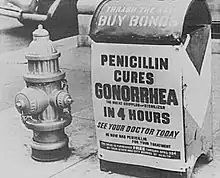

L'évolution de la résistance aux antibiotiques du germe a modifié sa prise en charge suivant l'époque : de la sulfonamide à la fin des années 1930, on est passé à la pénicilline à doses croissantes, cette dernière n'étant plus utilisée à partir des années 1980. Les fluoroquinolones et les céphalosporines ont pris alors le relais, avec l'apparition de résistances dès les années 1990[48]. Cette évolution pose un réel problème de santé publique d'autant que certaines souches peuvent être résistantes à plusieurs antibiotiques à la fois. La proportion de ces dernières varie de façon importante suivant les pays. La résistance aux quinolones s'est largement répandue[16].

Depuis la fin des années 1980, la maladie devient plus difficile à soigner. En 2017, un article paru dans Nature[52] rappelle que la gonorrhée devient aussi incurable qu’au début du XXe siècle, avant l’apparition des premiers antibiotiques capables de la traiter.

Elle est devenue moins préoccupante pour la santé publique des années 1920 aux années 1980 (où les médecins disposaient de plusieurs antibiotiques efficaces), mais des résistances (aux sulfamides) sont signalées dès les années 1940[23], faisant à nouveau progresser la maladie notamment dans les populations pauvres (y compris aux États-Unis dans les populations pauvres et rurales par exemple[24]). La maladie redevient au début du XXIe siècle un problème grave de santé publique. En 2017, elle figure en tête de la liste des microorganismes pour lesquels l’OMS et l’initiative de l’ONG « Médicaments pour les maladies négligées » (DNDi ; Drugs for Neglected Diseases initiative) cherchent à inventer et développer de nouveaux médicaments efficaces et de meilleures techniques de prévention (peut-être à un coût moindre que par les moyens classiques de l'industrie pharmaceutique[25])[26].